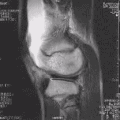

MRI

Both anterior cruciate ligament (ACL) and posterior cruciate ligaments (PCL) are hypointense on both T1 and T2 weighted images of MRI. However, some high signal striations are often seen at the distal part of the ACL, making ACL higher intensity than PCL on MRI scans.[20]